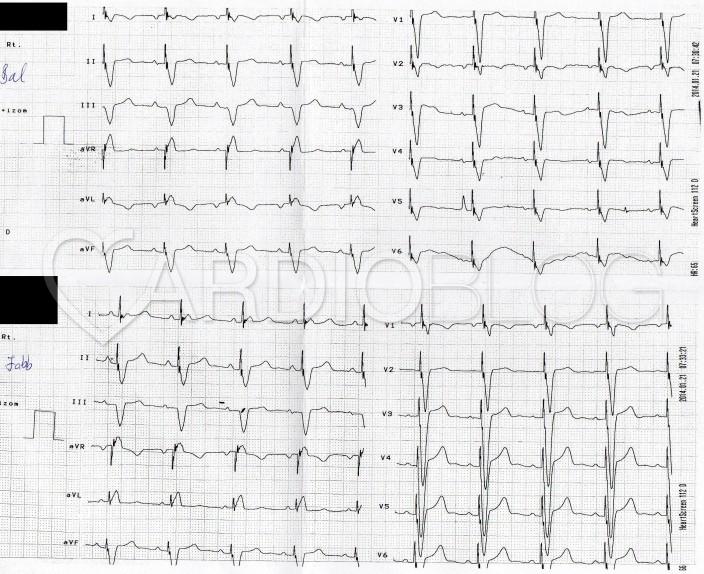

Harmadfokú AV blokk, junkcionális pótritmus BTSZB-kal levezetve dextrocardiában

Tény, hogy valóban elég cifra EKG-t sikerült így az évad végére találni. Szerintem az érdekessége főleg az, hogy egy dextrocardiás beteg regisztrátumát látjuk. Ezt főleg az I. elvezetésben látott negatív P- hullám és QRS alapján gondolom. Valamint abból, hogy V1-től V6-ig folyamatosan csökken a QRS-ek amplitúdója. Emiatt nem gondolnám hogy kábelcseréről van szó. A változó P-Q távolságok harmadfokú AV blockra utalnak és a QRS széles. Csakhogy a széles QRS kamrai pótritmust jelez, ami 40/ percnél nemigen szokott több lenni, itt pedig 75 körüli a kamrai frequencia. Emiatt úgy gondolom, hogy az ingerületvezető rendszer nem túl disztális részéről ered az inger, talán a junkcióból, és blokkosan vezetődik le. Ezen a felvételen talán az aVR-t lehetne equifázisosnak kinevezni, de az alternáló QRS-ek miatt ez sem egyértelmű. ( számomra ). Emiatt nehéz megmondani, hogy milyen blokkról van szó. Bár a BTSZB EKG jelei közé tartozik az M alakú széles R hullám az I-aVL, V5-6 elvezetésekben ám itt éppenhogy QS komplexumot látunk. De mivel itt tükörképben kell gondolkodni, megkockáztatom a balszárblokk diagnózist is.

A pótritmus relatíve gyors frekvenciája junkcionális ingerképzésre utalt. A BTSZB felismerésében a natív EKG-n a V1-2-ben látható típusos mintázat lehetett segítségünkre. Ha az elektródákat fordítva rakjuk fel (nyilván nemcsak a két kar elektródákat kell felcserélni, hanem a jobb oldalra kell felhelyezni a mellkasi elvezetéseket), akkor már jól a szemünk elé tárul a BTSZB-szerű kép. (Utólag mindig könnyű okosnak lenni.)

Érdemes megfigyelni, hogy a végtagi elvezetések relatíve nagy ampltúdójú P hullámait olykor a gép QRS-nek számolja, ezért a valósnál többnek jelzi a kamrafrekvenciát. (A fordítva felhelyezett elvezetéseknél a duplájának.)

Ha 25 mm/sec sebességgel megy a szalag (a P hullámok szélessége alapján ez a valószínű), akkor a kamraferquentia nem a szalag szélén látható 88/min, hanem 54/min és a pitvari frequentia 75/min.

Végezetül, íme a DDD pacemaker beültetés után készített EKG-k (hagyományosan, illetve fordítva felhelyezett elvezetésekkel):